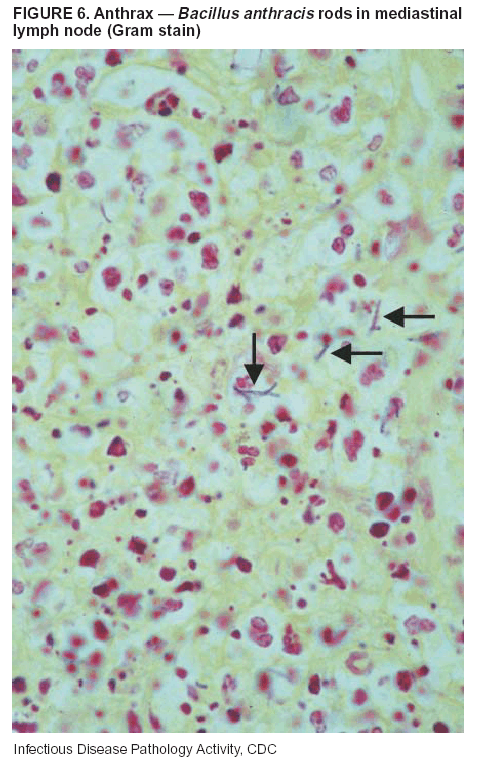

Pathologic Findings. Anthrax has three pathologic forms. Cutaneous anthrax is characterized by an eschar that forms where the bacteria entered the skin (Figure 2). Microscopically, the epidermis has necrosis and crusts, whereas the dermis demonstrates necrosis, edema, hemorrhage, perivascular inflammation, and vasculitis. The lymph nodes that drain the skin site eventually become enlarged, necrotic, and hemorrhagic. Gastrointestinal anthrax is distinguishable by hemorrhagic ulcers in the terminal ileum and caecum accompanied by mesenteric hemorrhagic lymphadenitis and peritonitis. Inhalational anthrax is characterized by hemorrhagic mediastinal lymphadenitis (Figure 3) accompanied by pleural effusions. Histologically, lymph nodes have abundant edema, hemorrhage, and necrosis with limited inflammatory infiltrate (Figure 4) (18,25--29). As any of the three anthrax forms progresses, the bacteria can spread to abdominal organs, producing petechial hemorrhages, and to the central nervous system, producing hemorrhagic meningitis (i.e., cardinal's cap) (Figure 5).

Diagnostic Specimens. Performing a complete autopsy with histologic sampling of multiple organs will help determine the distribution of bacilli and the portal of entry. The specimens that harbor the highest number of B. anthracis organisms vary by the pathologic form of anthrax. For example, diagnosis of cutaneous anthrax requires skin samples from the center and periphery of the eschar, whereas for inhalational anthrax, pleural fluid cell blocks, pleura tissue, and mediastinal lymph nodes have the highest amounts of bacilli and antigens.

Diagnostic Tests. If the patient has not received antibiotics, bacilli can be observed in tissues with H&E, Gram, and silver impregnation stains and IHC assays (Figures 6 and 7). However, after antibiotic treatment has been instituted, only silver stains and IHC assays will highlight the bacilli. IHC assays for B. anthracis can demonstrate bacilli, bacillary fragments, and granular bacterial fragments in formalin-fixed tissues, even after 10 days of antibiotic treatment. Although a DFA test is available for B. anthracis, it is not used on formalin-fixed tissues.